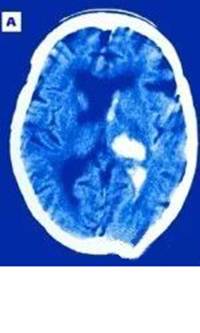

下图显示的是脑出血患者1小时和6小时的脑内血肿变化(中间白色为在CT上显示的血肿)。

(发病1小时的血肿大小)

(发病6小时的血肿大小)